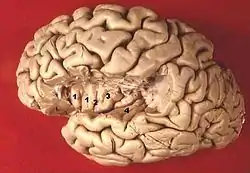

![]() Human brain view on transverse temporal and insular gyri (gyri temporales transversi are #4) | |